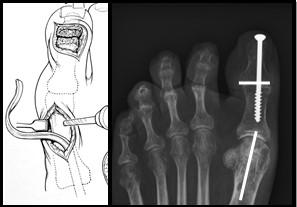

Extenderende Osteotomie 1e straal

Hierbij wordt de grote teen omhoog geplaatst door een botwigje uit te zagen aan de basis van de grote teen. Door dit wigje te verwijderen kan de grote teen omhoog komen waardoor de holling in de voet minder wordt. De voet wordt dus platter en beter belastbaar. Op de plaats waar we het botwigje hebben verwijderd plaatsen we een RVS schroefje en ijzerdraadje om het middenvoetsbeentje van de grote teen op de juiste positie te houden. Zodra het bot genezen is, is de schroef niet meer nodig en kan bij klachten evt worden verwijderd.

Figuur 4: Het bovenste linker plaatje is een schematische weergave van de “osteotomie”. Het driehoekje bij de pijl wijst naar de wig die uitgezaagd wordt. Het plaatje eronder laat de situatie zien na verwijderen van het wigje. Het middelste plaatje laat een voetfoto van een patiënt zien voor de operatie, de witte streep is de plaats van het litteken. het meest rechtse plaatje is na de operatie. Bij de pijl zie je de schroef en het ijzerdraadje om de botdelen op de juiste positie te houden.

Jones Procedure

Bij de Jones procedure wordt de lange strekpees van de grote teen verplaatst van het eindkootje naar het middenvoetsbeentje van de grote teen. De beide kootjes van de grote teen worden aan elkaar vastgezet met een schroef. Deze procedure zorgt ervoor dat de strekpees van de grote teen de teen niet meer doet klauwen maar zorgt juist voor een omhoogwaartse beweging van de grote teen. Dit gaat weer de holvoet tegen.

Figuur 5: Op het linker plaatje is de grote teen zichtbaar. Er worden 2 littekens gemaakt. De pees wordt losgehaald bij het eindkootje en door het middenvoetsbeentje gevlochten door een boorgat. Op de rechter foto is de schroef zichtbaar die beide kootjes aan elkaar verbindt. Deze wordt vanuit het puntje van de teen geboord middels een (klein) 3e litteken. De witte streepjes geven de locatie van de andere 2 littekens aan.